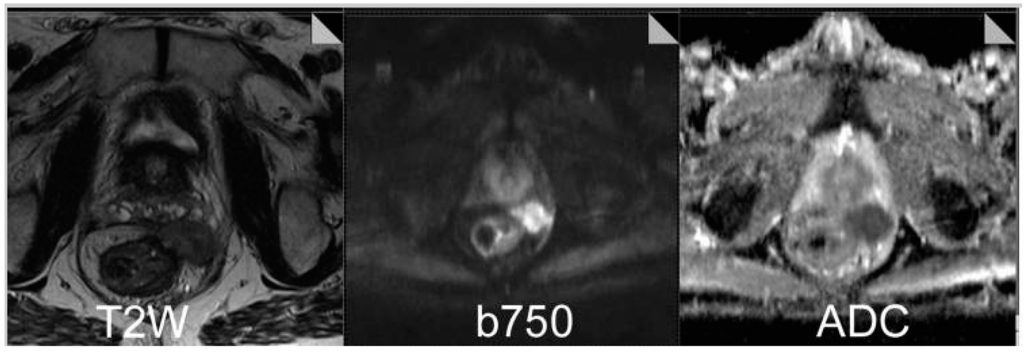

2.2. Functional Imaging with MRI

3. Rectal Cancer

- Lambregts, D.; Vandecaveye, V.; Barbaro, B.; Bakers, F.C.H.; Lambrecht, M.; Maas, M. Diffusion-weighted MRI for selection of complete responders after chemoradiation for locally advanced rectal cancer: A multicenter study. Ann. Surg. Oncol. 2011, 18, 2224–2231. [Google Scholar] [CrossRef] [PubMed]